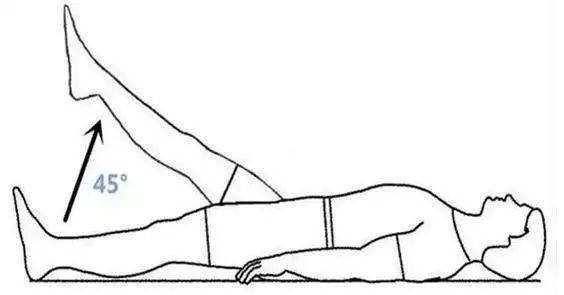

患者在臥床休息期間為了防止神經根粘連,加強腰椎的穩(wěn)定性,可在床上做直腿抬高練習、“五點支撐”、 “三點支撐”等鍛煉方式進行功能鍛煉。